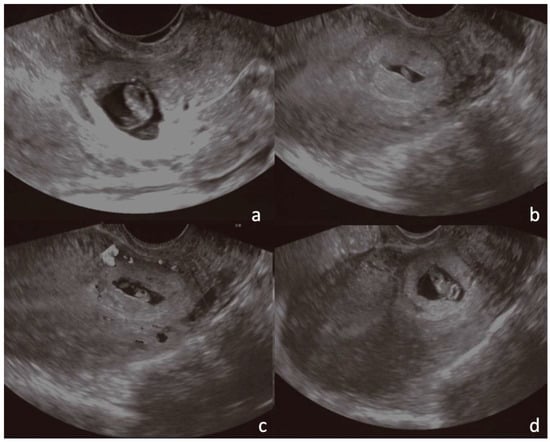

4.1.1. Case 1 (CSP Type I)

4.1.2. Case 2 (CSP Type II)

4.1.3. Case 3 (Low-Implanted Pregnancy)